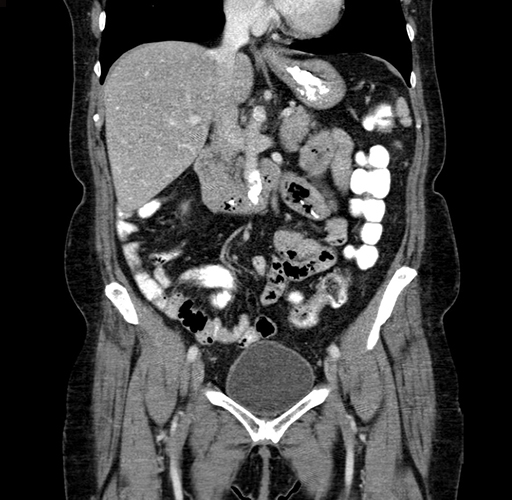

Pre-Chemo: Coronal Venous

Coronal Venous